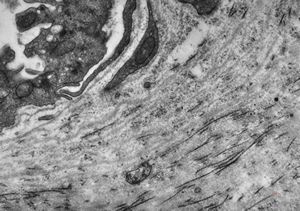

F, 39y. | collagenous and elastin fibers from corium

F,68y. | collagenous and elastin fibers from corium